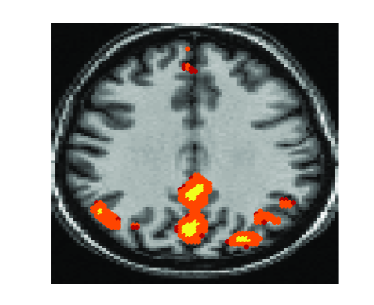

In this section we evaluate the performance of the proposed joint

matrices diagonalization algorithm on a resting state fMRI experiment

data set [20]. Data-driven methods were successfully

suggested and applied to fMRI data analysis. These methods consider

the fMRI time series measured at each voxel as a mixture of signals

localized in a small set of regions and other simultaneous

time-varying effects. They isolate the spatial brain activity by

estimating a mixing matrix and the sources that define the spatially

localized neural dynamics. Most data driven fMRI analysis methods

use a data matrix Y formed by vectorizing each time

series observed in every voxel creating a matrix Y of

dimension where is the number of time points and

the number of voxels, .

These methods consider Y as

the mixture and factorize it into latent sources through the

decomposition into matrices , a

mixing matrix A and a source matrix

X. Data-driven methods are suitable for the analysis of

fMRI data as they minimize the assumptions on the underlying structure

of the problem by decomposing the observed data based on a factor

model and a specific constraint. Different constraints have led to

different data-driven methods. For example, the maximum variance

constraint has led to principal component analysis (PCA)

[11], the independence constraint has led to independent

component analysis (ICA) [14] and sparsity constraint has

led to dictionary learning [13].

Recently, ICA has become a widespread data-driven method for fMRI analysis. It has led to temporal ICA (tICA, for the format of the data described above) and spatial ICA (sICA) [14]. In this experiment we applied the proposed joint diagonalization approach on twenty correlation matrices of size obtained from a data set of size . This data set was constructed from the slice 41, which we know contains the activated regions of the default mode network (DMN) [20]. For comparison we used the tICA approach. We can observe from figure 4 that both the proposed approach and tICA recovered the connected regions of the DMN; the posterior cingulate cortex (PCC), medial pre-frontal cortex (MFC), and right inferior parietal lobe (IPL). Since there is no gold standard reference for DMN connectivity available, we relied on the similarity of temporal dynamics of DMN based modulation profile with PCC representative time-series. The similarity measure used was correlation and it was estimated as for all the algorithms.